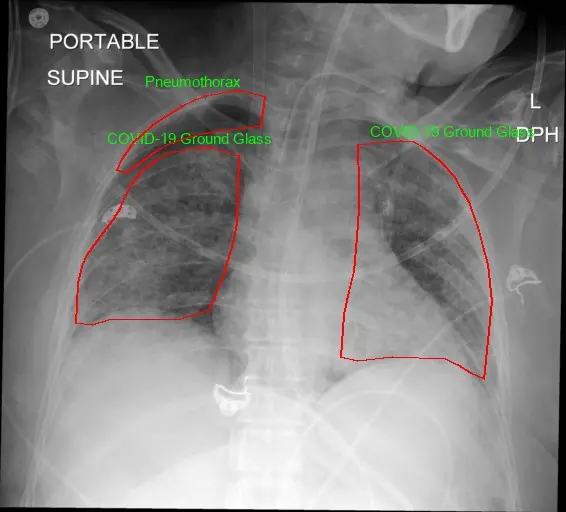

Caddie’s SIFT™ is the only fully automated annotation tool in the market capable of identifying 66 comorbidities on Chest X-ray and 44 abnormalities on Chest CT simultaneously. Designed specifically for chest X-ray and CT imaging, SIFT™ provides rapid, accurate, fine-grained image labeling and annotation to assist annotators in identifying abnormalities and their corresponding boundaries.

Providing Initial Type of Abnormalities SIFT™ can automatically detect and classify ROIs into specific types of abnormalities (“Predicted Disease”). It can predict 66 different types of abnormalities and recommend several options if the original prediction score is not high enough. Annotators can easily confirm or reject the type using SIFT’s interface.

- Boundary Coordinates: SIFT™ can automatically draw ROI boundaries and predict location coordinates. Annotators can accept or edit the boundaries using the SIFT™ GUI.

- Identifying Additional Abnormalities: SIFT™ automatically identifies and delineates additional abnormal regions and boundaries on chest X-ray images.

- Confidence Scores: SIFT™ generates confidence scores for each AI-specified ROI and predicted disease.

It generates fine-grained boundaries and precise locations of lesions.